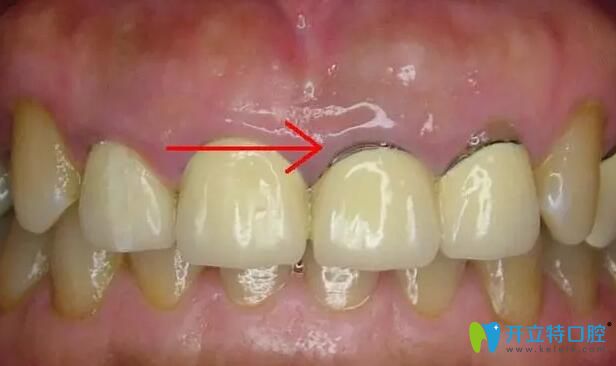

烤瓷牙圖片

1、比較常見(jiàn)的牙齦黑線:這是鎳鉻烤瓷牙和鈷鉻烤瓷牙比較常出現(xiàn)的情況,這是因?yàn)閮?nèi)冠的非貴金屬材料在口腔內(nèi)氧化變成的灰色氧化物,時(shí)間長(zhǎng)了就會(huì)沉淀在牙齦上。如果不及時(shí)拆除,有可能會(huì)出現(xiàn)牙周炎、牙齦炎嚴(yán)重的也會(huì)導(dǎo)致牙齒脫落。

烤瓷牙牙齦黑線